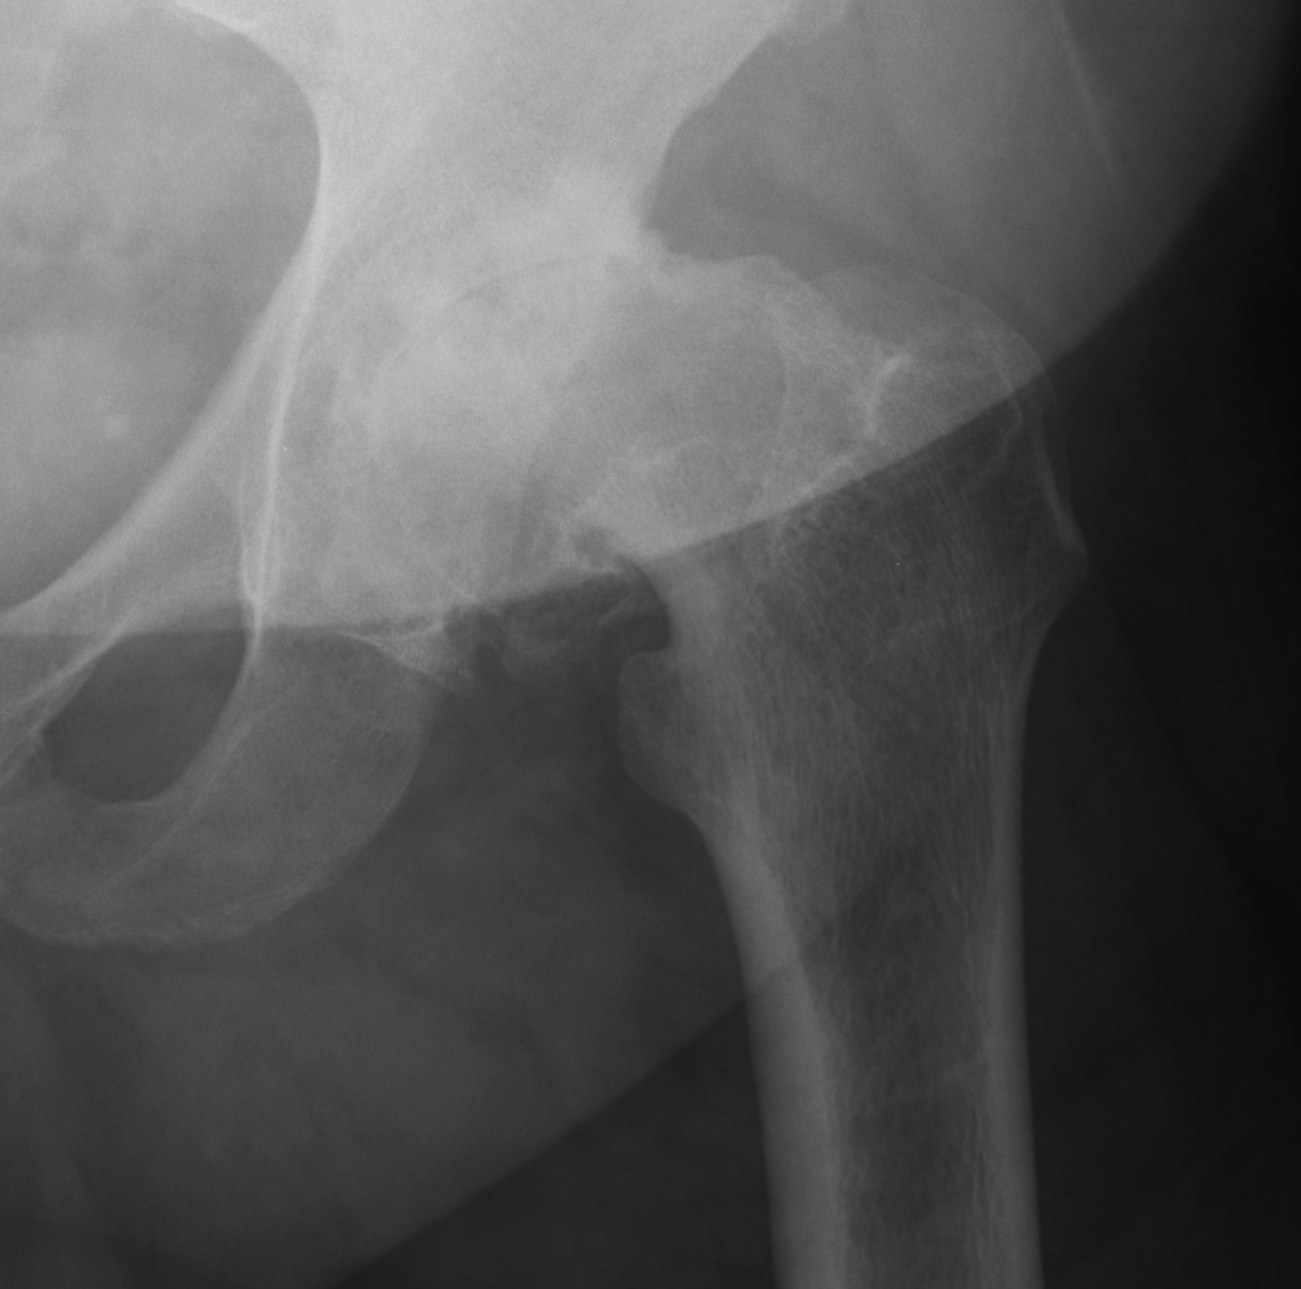

Osteoarthritis

- abnormal morphology

- loss of head neck offset

- bony impingement on acetabulum

OA post SCFE AVN post SCFE